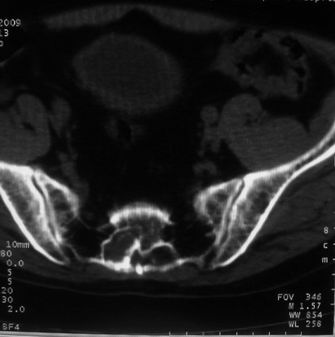

男,85岁,排尿困难。骶椎有问题吗?

前列腺明显增大,突入膀胱,各叶比例协调,密度均匀,精囊腺及精囊角正常;考虑良性增大。

骶骨没有看到明显异常。

1)考虑前列腺增生症并阻塞性膀胱炎。2)骶椎右侧类似囊状骨质密度减低区,边缘骨质硬化,其内为软组织密度影填塞,相邻之骶椎椎管受压变形;考虑为骶椎右侧囊肿或神经纤维瘤。

建议:行mri检查。

1)前列腺明显增大,突入膀胱,各叶比例协调,密度均匀,精囊腺及精囊角正常;考虑前列腺增生症并阻塞性膀胱炎。2)骶椎右侧类似囊状骨质密度减低区,边缘骨质硬化,其内为软组织密度影填塞,相邻之骶椎椎管受压变形;考虑为骶椎右侧囊肿或神经纤维瘤。